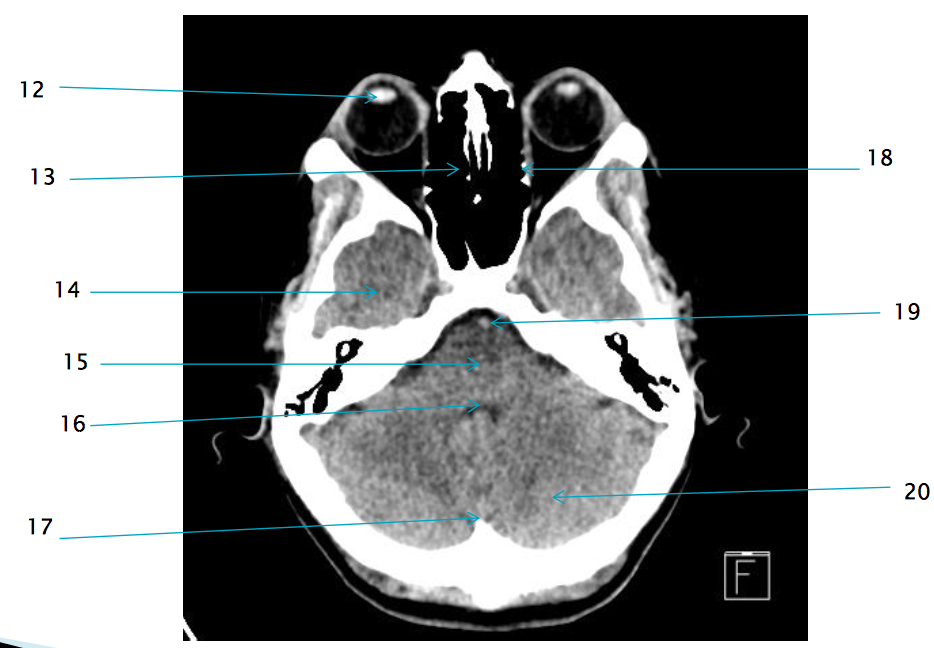

12

lens of R eye

13

ethmoid air cells R

17

internal occipital protuberance

19

basilar artery